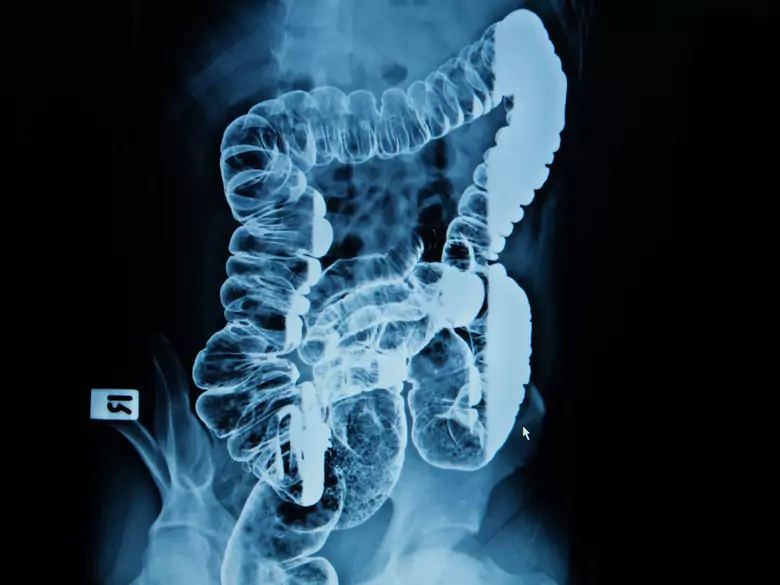

Intestinos